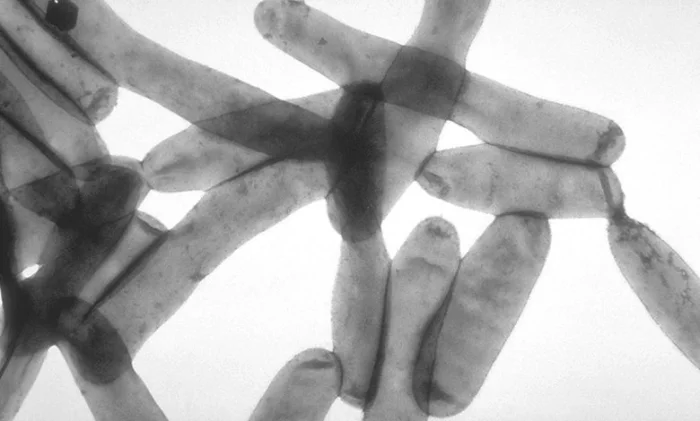

Бактерия, которая повсеместно распространена по всему миру

Бактерии Легионеллы процветают во всех типах пресноводных сред (особенно если вода теплая) или в заболоченных местах, при температуре от 20 до 50 °C. Их можно найти в душевых насадках и кранах, спа, градирнях, резервуарах с горячей водой, декоративных фонтанах или водопроводных системах в больших зданиях.

Вдыхание (не проглатывание) капель зараженной воды вызывает инфекцию, которая может принять форму «болезни Легионеров» — тяжелой респираторной инфекции с неврологическими и пищеварительными проблемами и почечной недостаточностью — или более легкой формы, известной как «Понтиакская лихорадка». Впервые болезнь легионеров была зарегистрирована в 1977 году в Филадельфии, когда около 200 человек, участвовавших в съезде Американского легиона, заболели тяжелой пневмонией.